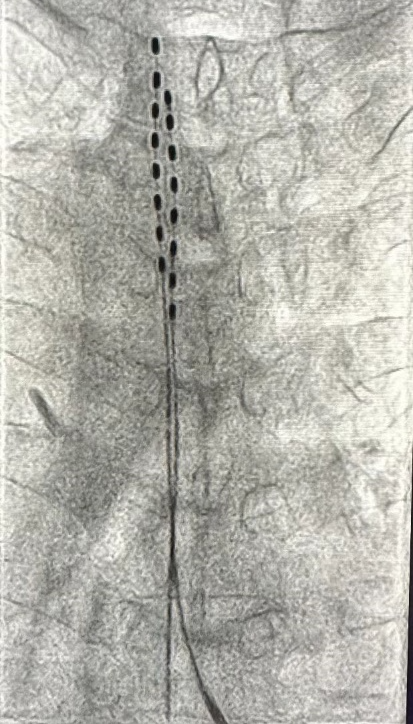

经过一系列仔细的评估,在患者及家属同意下,疼痛科副主任刘永峰决定为冯阿伯进行目前先进的微创手术:脊髓电刺激。

刘永峰副主任介绍,脊髓电刺激(Spinal Cord Stimulation-SCS)疗法是通过植入脊髓硬膜外腔的电极导线将神经刺激器产生的电脉冲传至脊髓,对脊神经进行低压电刺激,对疼痛信号的传导进行干预和阻断,从而达到缓解疼痛的目的。脊髓电刺激是一种安全有效治疗多种类型慢性顽固性疼痛/慢性难治性疼痛的治疗方法。

「该项技术属于非常安全微创的技术,手术为局麻,患者全程可保持清醒。术后因刺激器是全植入式,伤口愈合后便可洗澡碰水,不影响生活。」刘永峰说道。